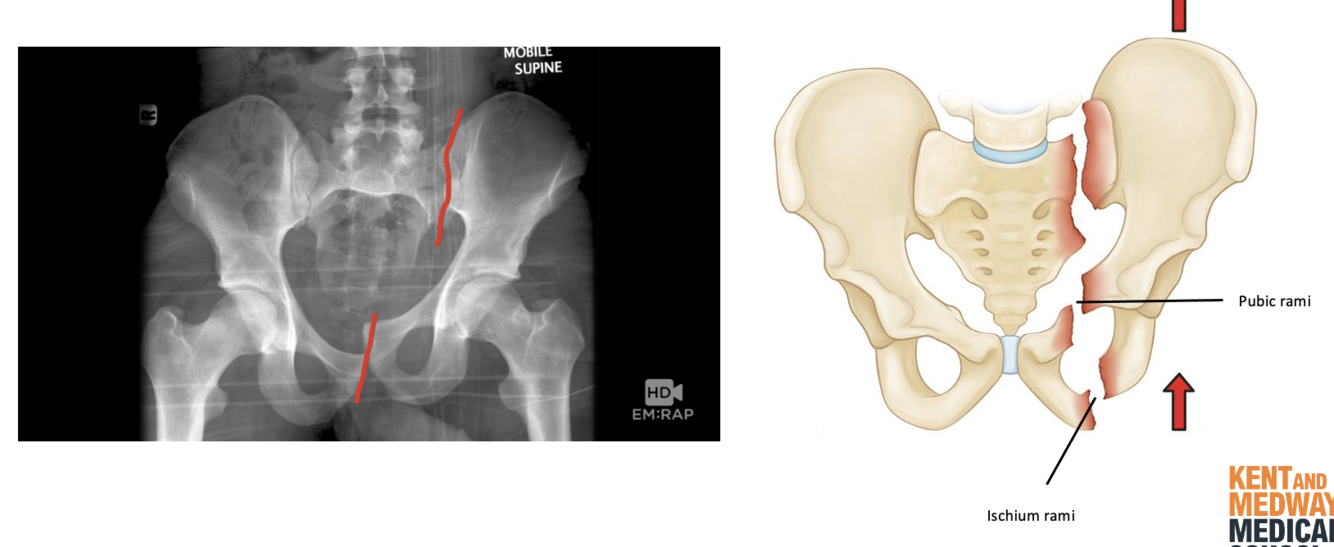

Pelvic fractures are common occurrences. What part of the pelvis are generally damaged?

1 - pubic and ischium rami

2 - ileum

3 - acetabulum

4 - sacroiliac joint

A